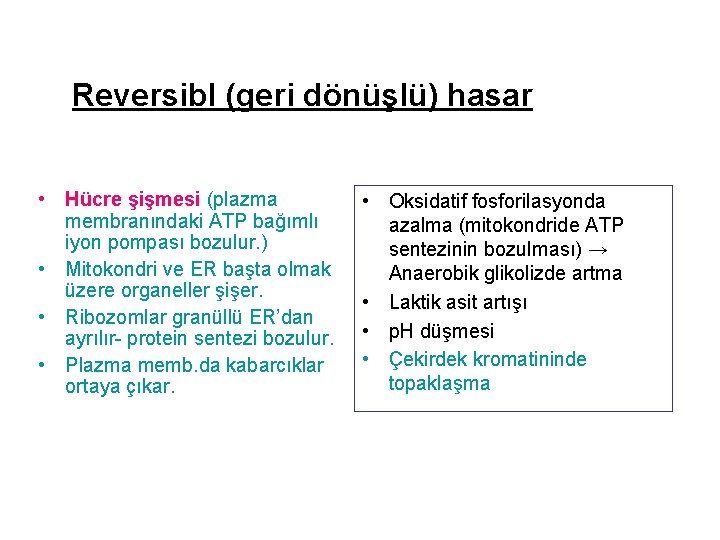

Reversibl (geri dönüşlü) hasar • Hücre şişmesi (plazma membranındaki ATP bağımlı iyon pompası bozulur. ) • Mitokondri ve ER başta olmak üzere organeller şişer. • Ribozomlar granüllü ER’dan ayrılır- protein sentezi bozulur. • Plazma memb. da kabarcıklar ortaya çıkar. • Oksidatif fosforilasyonda azalma (mitokondride ATP sentezinin bozulması) → Anaerobik glikolizde artma • Laktik asit artışı • p. H düşmesi • Çekirdek kromatininde topaklaşma